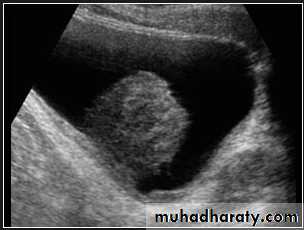

The kidney is bean shaped and has bright central echoes because of the fat surrounding the collecting system.

Normal renal ultrasound.

A longitudinal view of the right kidney was obtained by passing the sound beam through the right lobe of the liver. The kidney is seen behind this, outlined by the markers. The central bright echoes in the kidney are due to fat around the collecting system.